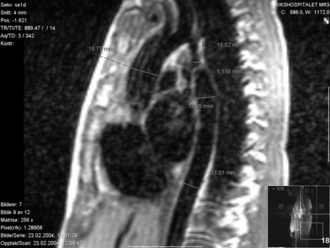

Koarktacija aorte je patološko suženje aorte na mjestu prelaska aortnog luka u nishodnu aortu, najčešće poslije izdvajanja lijeve podključne arterije. Na ovom mjestu se i fiziološki nalazi suženje aorte.

Patološko suženje aorte je u obliku nabora i nalazi se nasuprot duktusu arteriozusu.